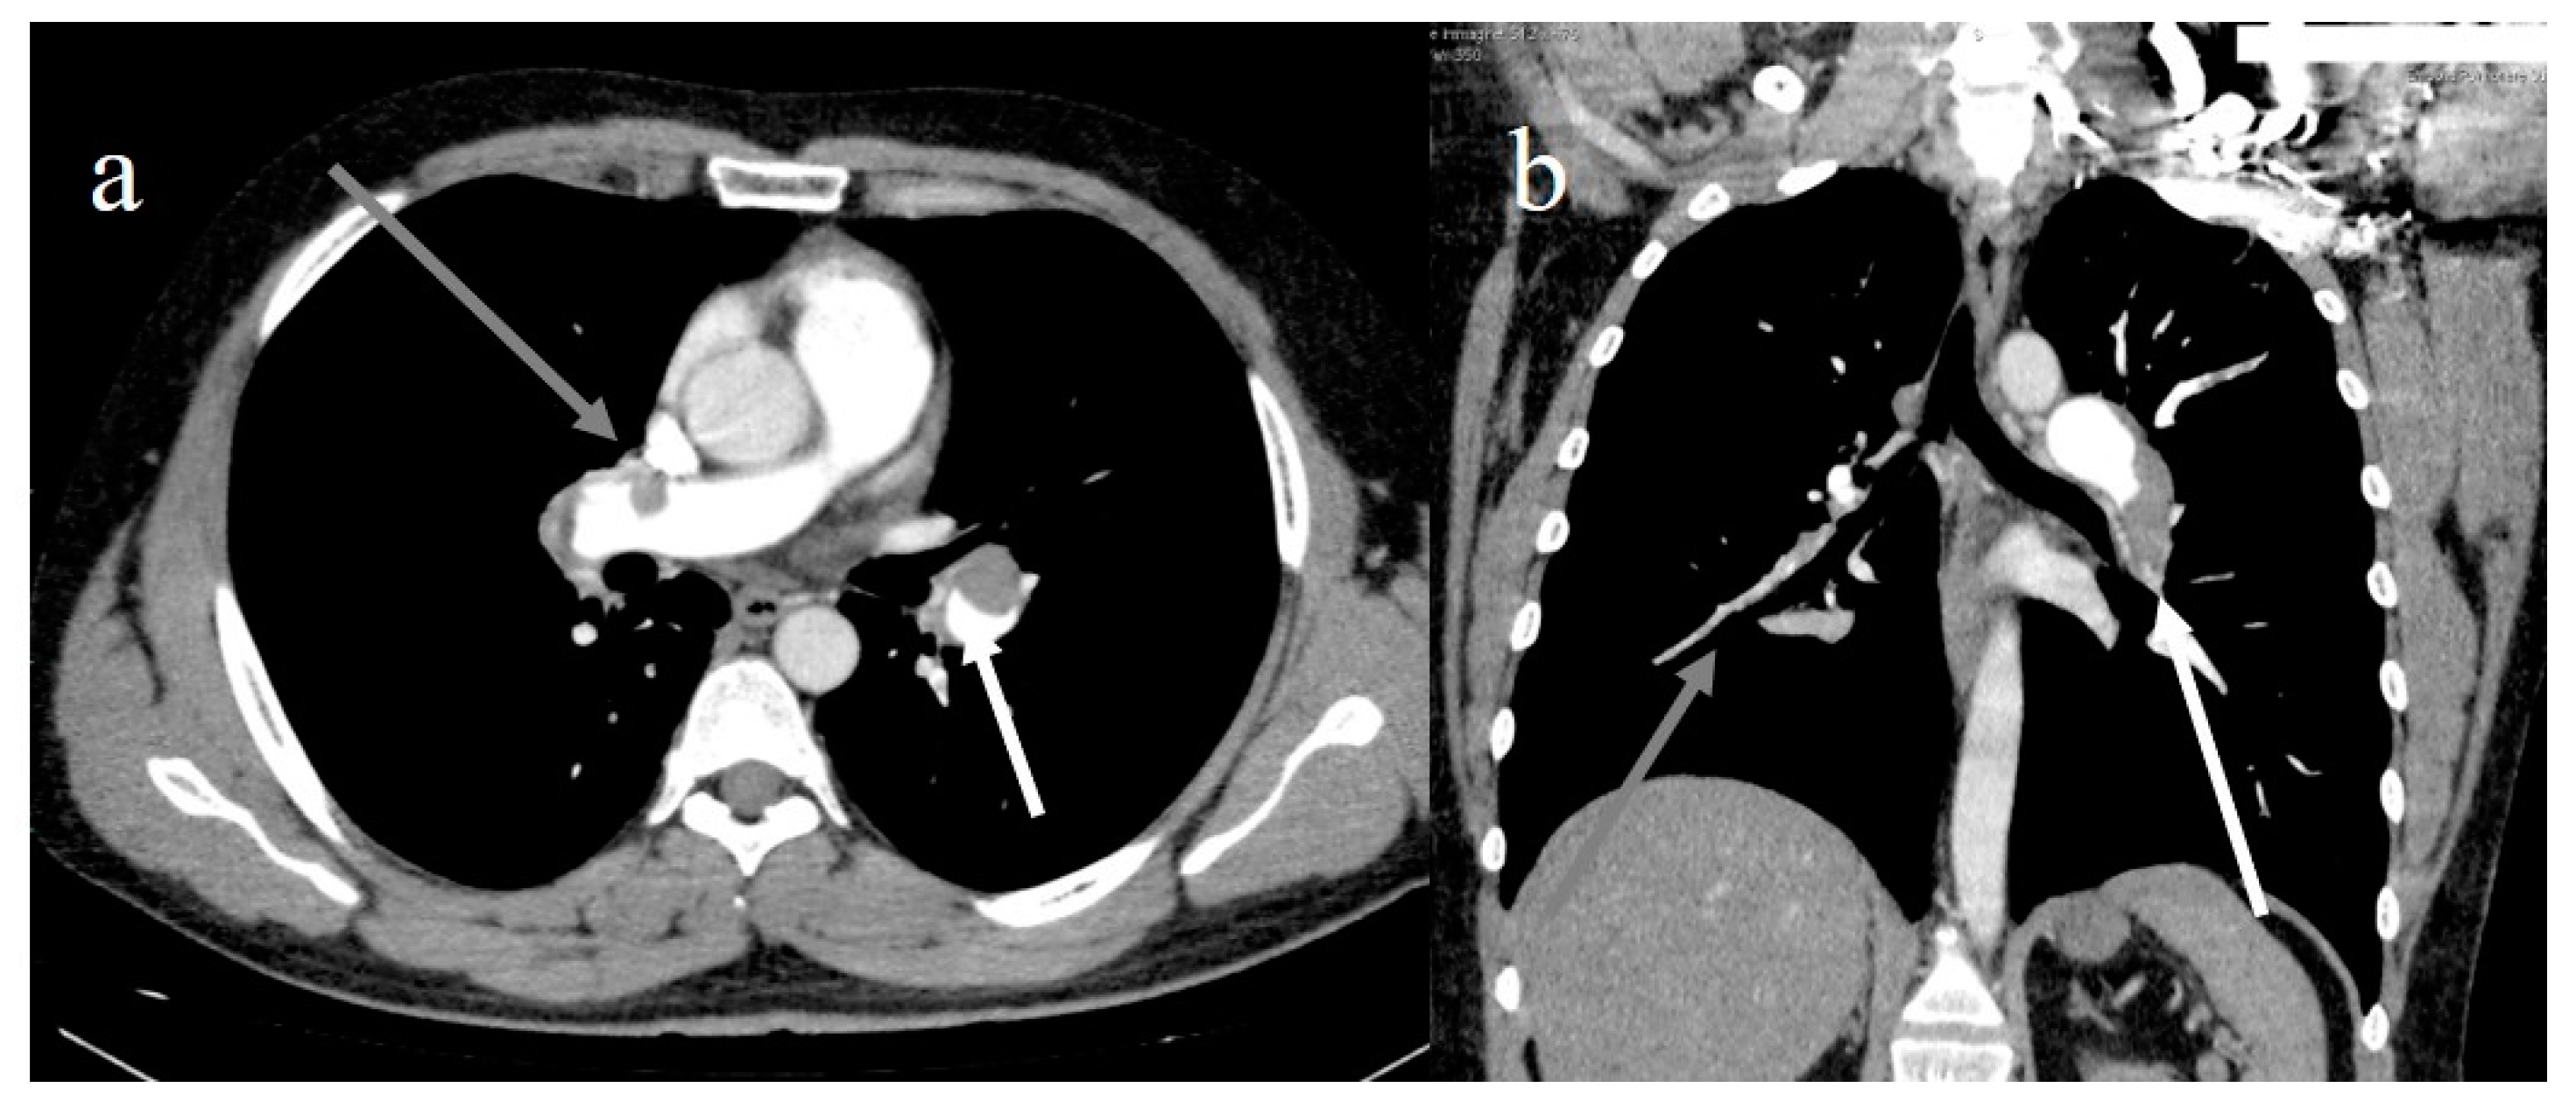

6. COVID-19 Complications

- Lang, M.; Som, A.; Carey, D.; Reid, N.; Mendoza, D.P.; Flores, E.J.; Li, M.D.; Shepard, J.-A.O.; Little, B.P. Pulmonary Vascular Manifestations of COVID-19 Pneumonia. Radiol. Cardiothorac. Imaging 2020, 2, e200277. [Google Scholar] [CrossRef]

- Ooi, M.; Rajai, A.; Patel, R.; Gerova, N.; Godhamgaonkar, V.; Liong, S. Pulmonary thromboembolic disease in COVID-19 patients on CT pulmonary angiography—Prevalence, pattern of disease and relationship to D-dimer. Eur. J. Radiol. 2020, 132, 109336. [Google Scholar] [CrossRef]

- Spagnolo, P.; Cozzi, A.; Foà, R.A.; Spinazzola, A.; Monfardini, L.; Bnà, C.; Alì, M.; Schiaffino, S.; Sardanelli, F. CT-derived pulmonary vascular metrics and clinical outcome in COVID-19 patients. Quant. Imaging Med. Surg. 2020, 10, 1325–1333. [Google Scholar] [CrossRef]